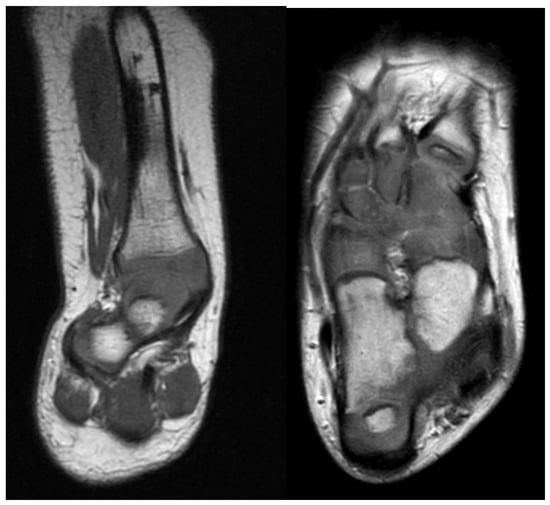

Magnetic resonance imaging (MRI) is not necessary in FH to differentiate between Paley types 1, 2, 3 or 4. This can typically be easily classified with clinical and radiographic examination only. An MRI becomes helpful in subclassifying Paley type 3 FH between a, b, or c and Paley type 4 by visualizing the mal-orientation of the tibial plafond present in types 3a and 3c and the malunited subtalar coalition in types 3b, 3c and 4 (Figure 2). It can also be helpful to identify aberrant vasculature [19,20] and the proximity of the posterior tibial vessels to the fibular anlage. Although it can also identify intra-articular pathology at the knee such as deficiency of the cruciate ligaments, this is best determined by physical examination. Computed tomography can be useful in older children whose bones are more ossified (Figure 3).

Figure 2.

Left is coronal cut of magnetic resonance imaging (MRI) through the ankle and subtalar regions. This shows a subtalar coalition with the Calcaneus to the side of the talus. The ankle has a ball and socket shape. Right is axial cut of MRI through the foot showing the malunited talo-calcaneal coalition with the calcaneus to the side of the talus. The talonavicular and calcaneocuboid coalitions are also seen.